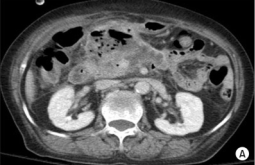

What's the Diagnosis?

Guess 1 / 5